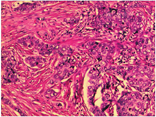

以病理诊断为金标准,病理分级参照2003年世界卫生组织(WHO)颁布的乳腺肿瘤组织学的分类标准,共3级,其中1级为恶性程度低的高分化,2级为中度恶性的中分化,3级为恶性程度最高的低分化[8]。

102例患者中≤40岁者33例,>40~50岁者27例,>50岁者42例;未绝经47例,已绝经55例;病灶大小:≤10 mm 19例,>10~20 mm 28例,>20~30 mm 35例,>30 mm 20例;钙化情况:有钙化61例,无钙化41例。最终经金标准确诊为乳腺浸润性导管癌者98例(见图2)。